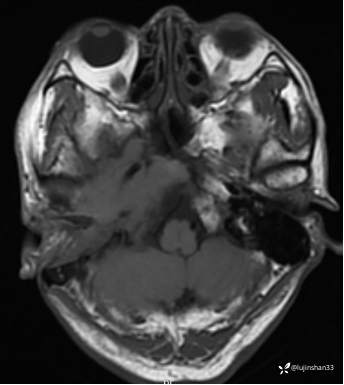

(2023-06-02 11:09,本院)磁共振(颅脑):1、右侧颞骨全切除术后改变,术区及相邻右侧斜坡、颞肌、咬肌、翼内外肌异常信号,考虑炎性肉芽肿性病变可能,请结合临床随诊复查;2、右侧小脑半球异常信号,考虑炎性病变可能;3、脑内散在缺血灶,软化灶形成;4、双侧蝶窦炎。

(2023-05-29 16:07,本院)CT颅脑:1、右侧颞骨全切除术后改变,术区见气体密度影,瘘管形成可能;术区多发软组织影,不完全除外炎性改变可能。2、左侧颞骨CT平扫未见明显异常。